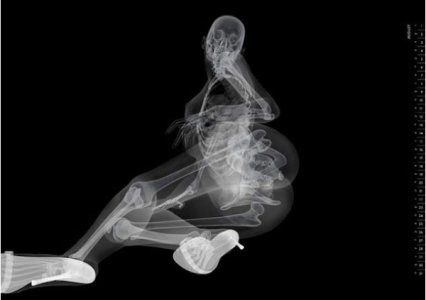

половой акт в разрезе, УЗИ, секс на рентгене

sex x-ray video

секс на томографе MRI

секс изнутри, половой акт в разрезе

как это снимал доктор Pek van Andel